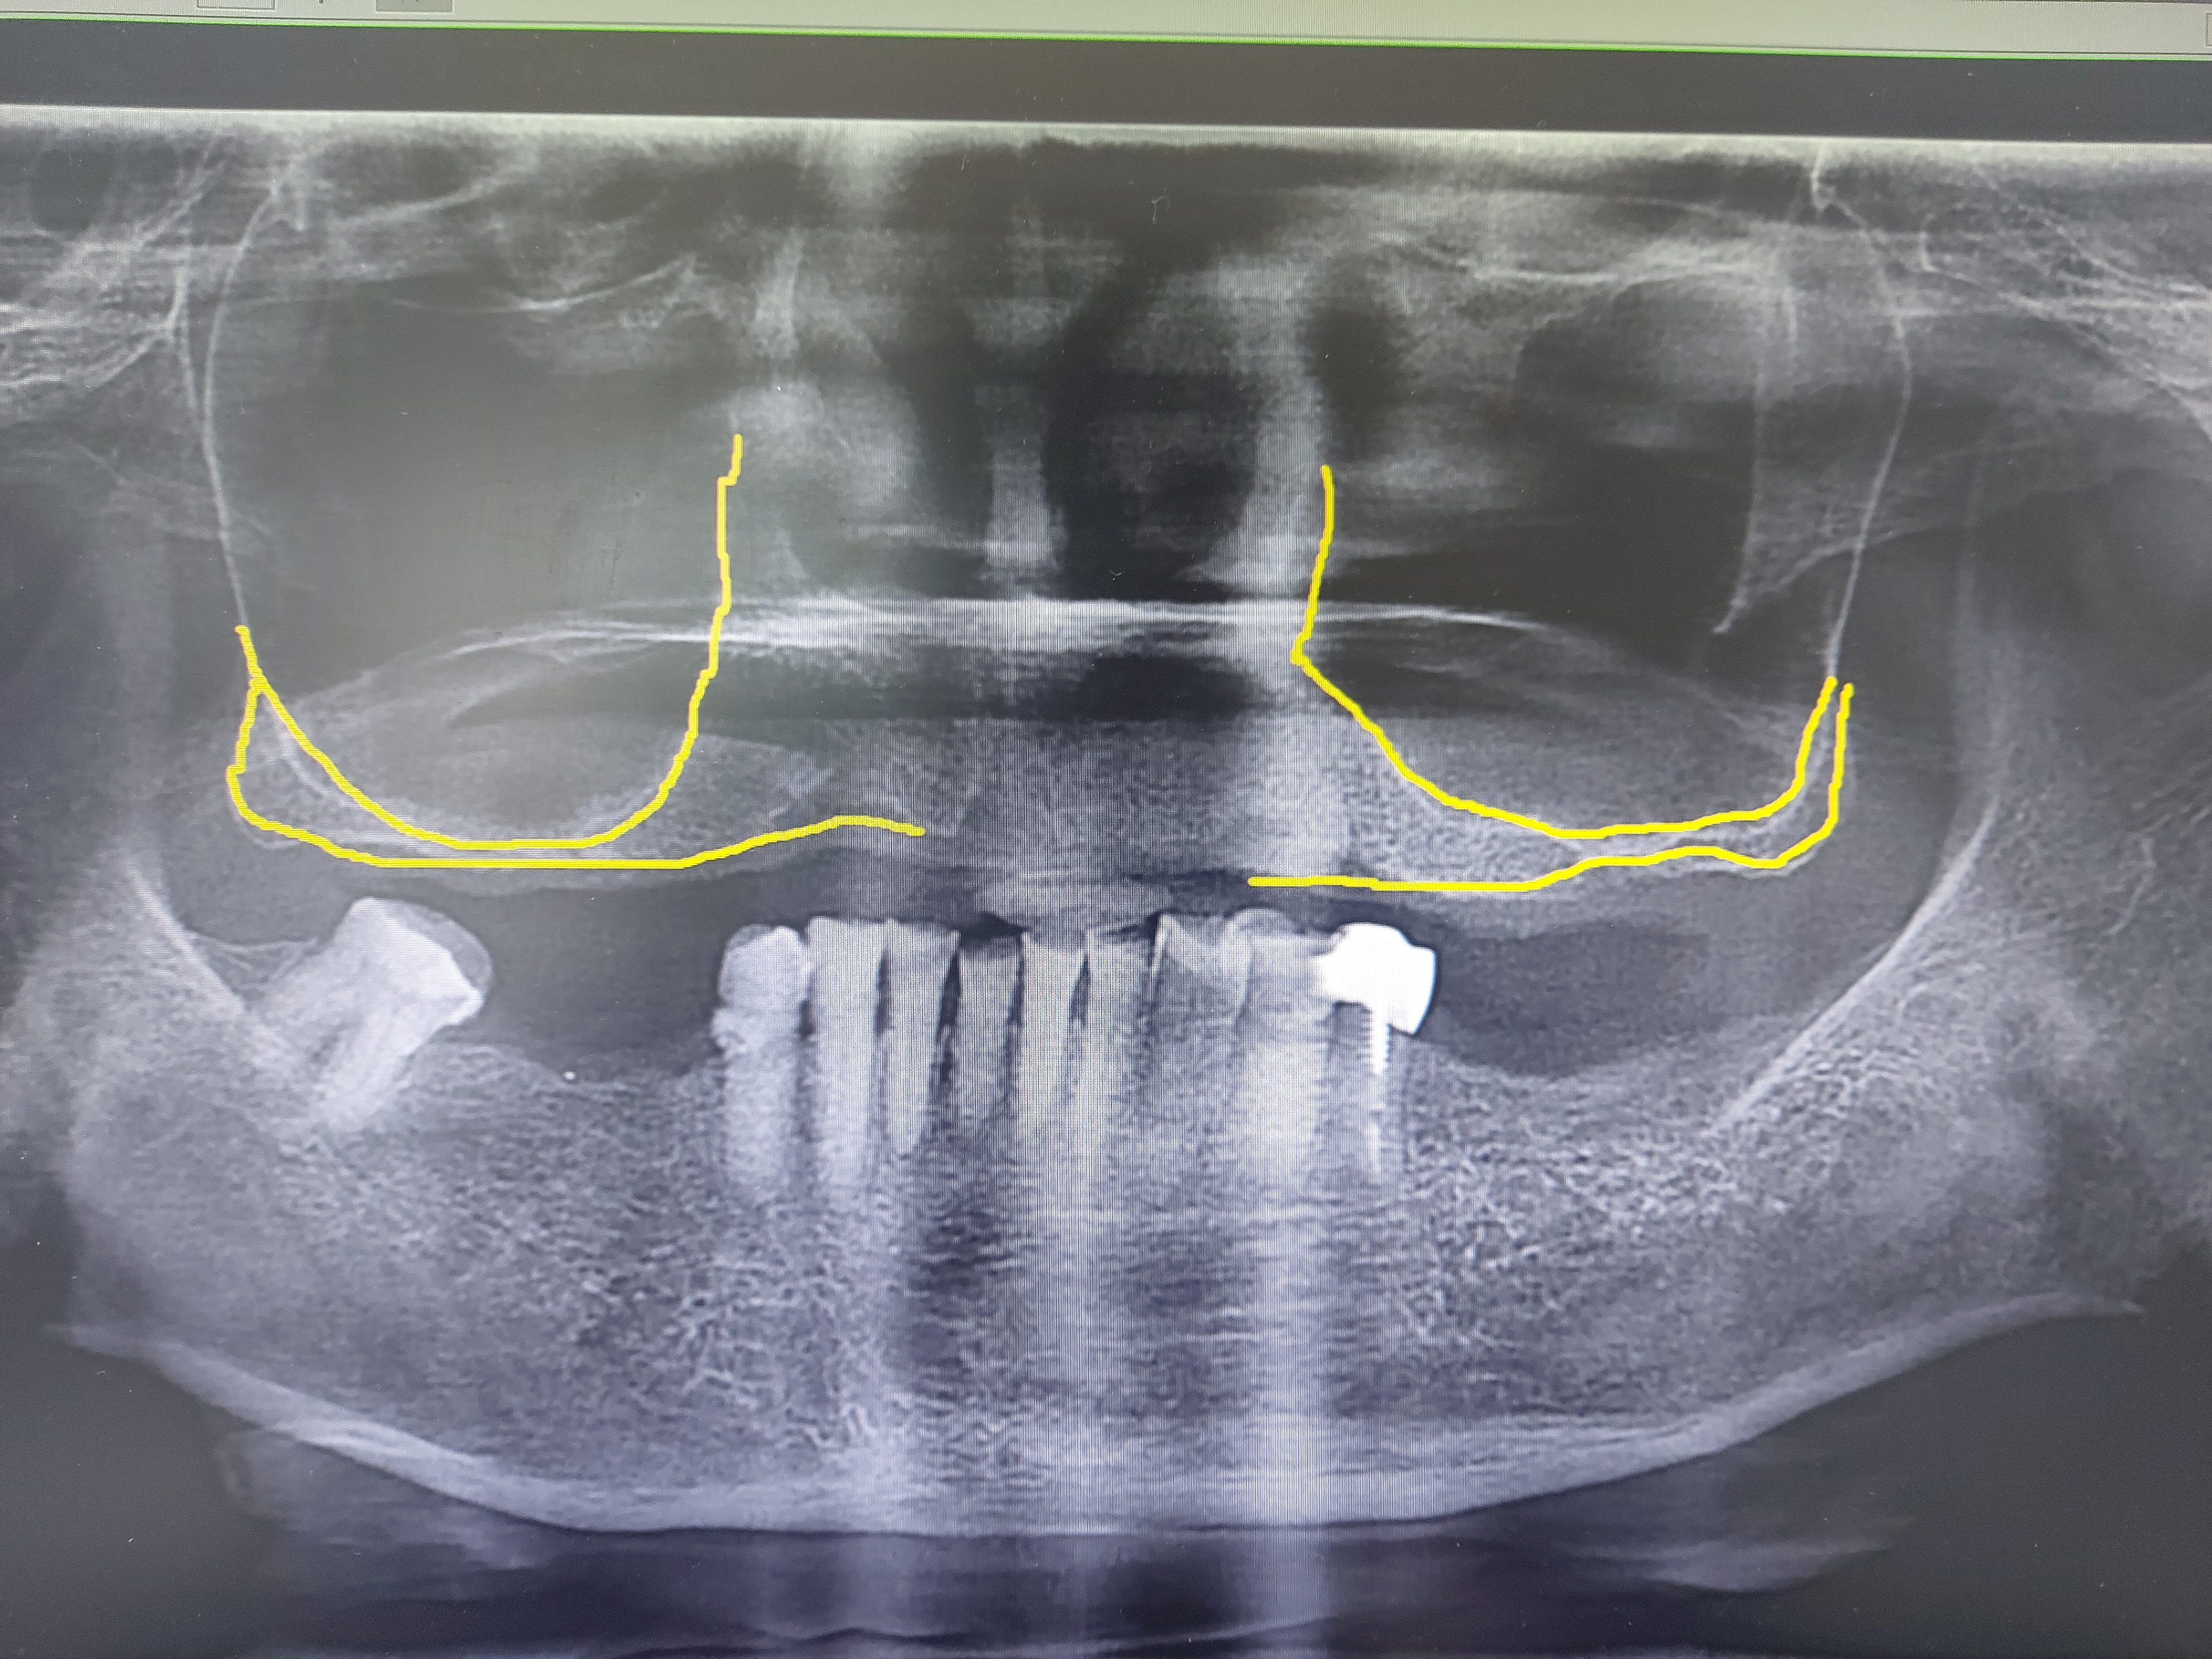

그럼에도 이 수술은 수술 자체의 술기도 중요하지만 상악동 내부의 정확한 이해와 수술 후 합병증이 발생하였을때 적합한 대응방법등 그리 만만한 수술은아닙니다. 이십년동안 저도 거의 천회이상 수술을 하였지만 잔존골이 많이 부족하거나 상악동 내부에 중격같은 특이사항이 있으면 수술전 심호흡을 하고 아주 차분하고 예민하게 접근합니다.

그렇기에 전문 장비로 충분한 진단과 환자분의 과거 병력등 기본적인것에 더 충실해야 하고 실수가 없어야 합니다.

상악동이 아랫쪽으로 내려오면 치조골의 높이가 부족해집니다. 임플란트를 식립할 만큼의 뼈가 부족해지기 때문에 내려앉은 상악동의 점막을 들어올려서 그 공간속에 뼈를 넣는 다음

임플란트를 식립하게 됩니다.

기본적으로 임플란트를 식립할 경우 최소 8~ 10 mm정도의 뼈가 필요하며 잔존골의 높이에다가 부족한 만큼 뼈를 이식하게 됩니다.